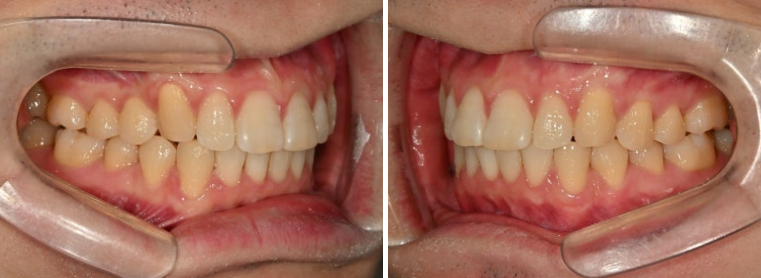

위아래 어금니 물리는 교합관계는 그래도 1급에 가깝습니다.

어금니 교합은 1급 교합관계를 보입니다.

앞니 뻗침은 좋아졌네요.